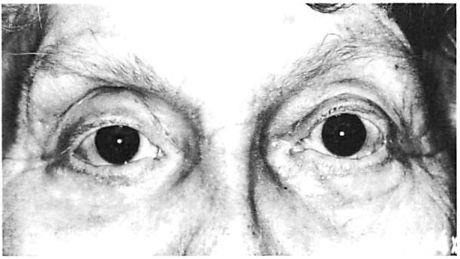

With experience, certain disadvantages of miniplate fixation of the mid and upper face have become evident. These have been related largely to scale, and include problems of palpability and visibility [10], especially around the orbit and forehead where the skin is thin (Fig 1). Sometimes these problems require a second operation for plate removal. Francel and associates [11] reviewed the incidence of miniplate removal in the treatment of 1,200 fractures in 507 patients managed in a trauma center setting. They found that 12% of all miniplates used subsequently required removal. Of this 12%, plate palpability or visibility prompted miniplate removal in 13%. In other words, between 1% and 2% of all miniplates placed were subsequently removed due to problems related to their prominence [11]. Review of our data reveals a similar incidence of plate removal for miniplate prominence in the treatment of 150 patients. Not considered in these statistics are patients who object to the prominence of their miniplates but are unwilling to undergo a second operation for their removal. Miniplates may be too large for the treatment of certain injuries. The hole spacing of miniplates may be too wide to fixate certain comminuted fractures. Plate configuration may also limit the contouring of miniplates and prevents ideal adaptation around the complex curvatures of the orbit.

Fig 1. Postoperative appearance of right and left orbital areas in a patient who underwent open reduction and internal fixation of complex facial fractures including fixation with a miniplate at the left zygomaticofrontal sulure. No surgery was performed in right zygomaticofrontal area. (A) Right zygomaticofrontal suture area, which did not undergo surgery. (B) Left zygomaticofrontal area. Arrows point to subtle contour of miniplate transmitted through thin skin envelope of lateral brow.